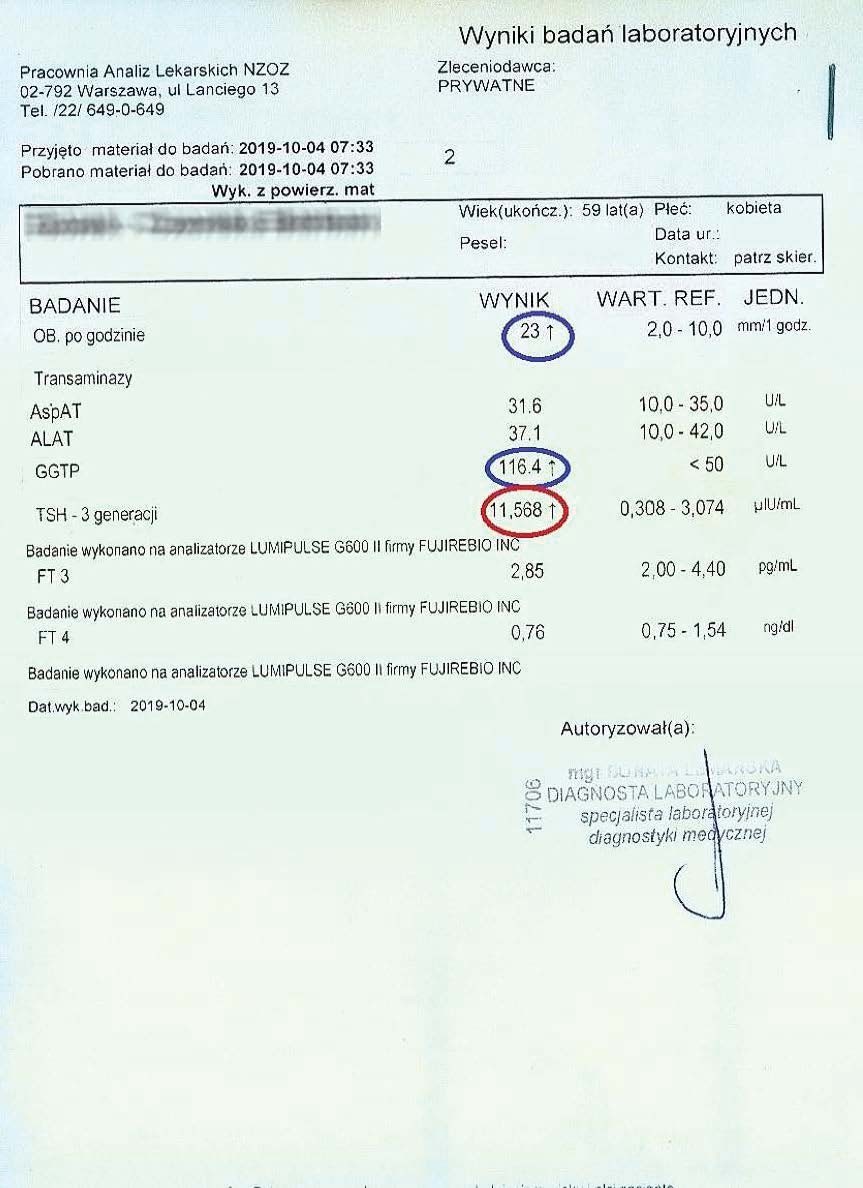

PRZYKŁAD EFEKTU PREPARATU NA NIEDOCZYNNOŚĆ TARCZYCY

Kobieta lat 59 z niedoczynnoscią tarczycy, bez przyjmowania lewotyroksyny. Kobieta przyjmowała preparat przez okres ponad 3 miesięcy. Przy zachowaniu naturalnego cyklu komórkowego i stałemu stymulowaniu mitochondriów osiągneła następujące wyniki kuracji:

Po zaobserwowaniu znacznej poprawy w ogólnym samopoczuciu, kobieta postanowiła wykonywać badania ze zwiększoną częstotliwością oraz kontrolę prób wątrobowych.

Po kolejnych dwóch miesiącach kobieta ponownie wykonała badania. Widoczne są: spadek TSH, obniżenie stanu zapalnego jak i spadek markeru wątrobowego GGTP.

Sukcesywnie co 2 miesiące można zaobserwować stały spadek parametrów zarówno wątroby jak i tarczycy. Kolejne badania potwierdzały dalszy spadek parametrów.

Po ponad roku kuracji badania wykazały dalszy postęp wycofania autoimmunologi tarczycy, potwierdzone również badaniem USG narządu.

Preparat wpływając na odbudowę mitochondriów zapewnił podłoże energetyczne do produkcji hormonów i odbudowy narządu. Brak ingerencji farmakologicznej wykazuje skuteczność nawet w podeszłym wieku, gdzie regeneracja jest wolniejsza a reakcje anaboliczne w znacznym stopniu spowolnione. Można zaobserwować także działanie ogólnoustrojowe obserwując spadek markeru wątroby, co jasno wykazuje poprawę funkcjonowania całego organizmu.